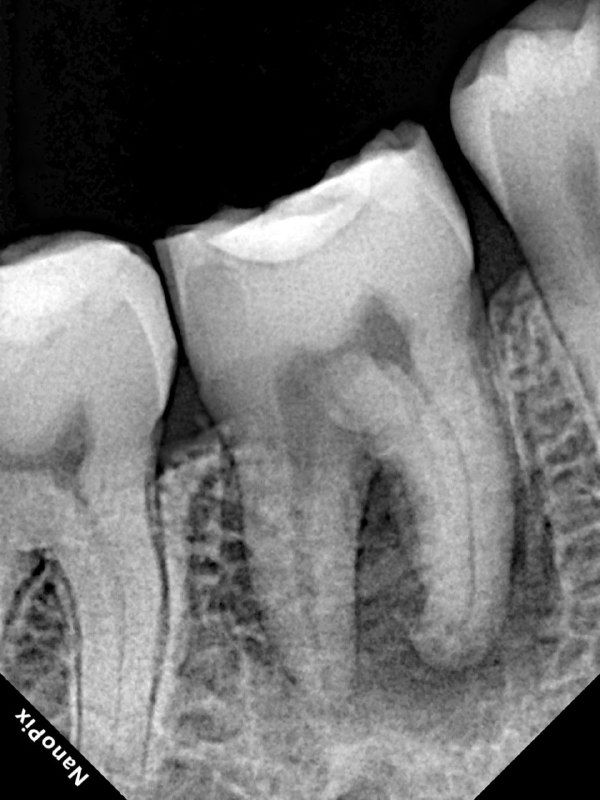

- 1️⃣ ВЫ ВИДИТЕ КРАЯ КОРОНКИ. Зачем это нужно? Потому что наружные края пульповой камеры ПОВТОРЯЮТ контур коронки зуба.

Пример: У 7-го зуба коронка вытянута с мезиально-щечного до нёбного бугра?

→ Полость доступа будет такой же вытянутой (от MB до P бугра) - 2️⃣ БОЛЬШЕ ПРОСТРАНСТВА ДЛЯ РАБОТЫ

Края пульповой камеры = контур коронки. Видите контур → делаете ТОЧНУЮ полость доступа → находите ВСЕ каналы